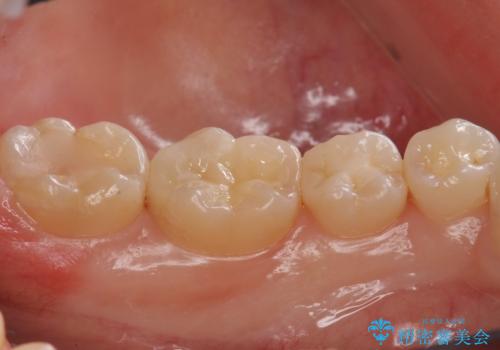

- 右下56 セラミックインレー 77000円×2本費用は治療当時の料金となります

メンテナンスで虫歯を発見することができたため、症状が出る前に治療を終えることができました。下の奥歯は笑った時に外からよく見える部分なので白く目立たない詰め物を入れることができて大変喜んでいただけました。